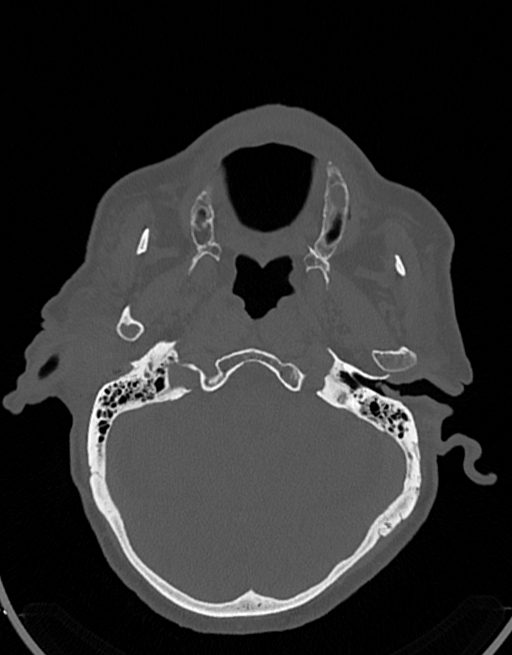

در سي تي اسکن اسپيرال نازو فارنکس با و بدون کنتراست (مولتي ديدکتور 16 با مقاطع ظريف و بازسازي هاي ساژيتال و کرونال):

– توده نسج نرمي به ابعاد mm 40 x 45 x 60 در ناحيه پاروتيد راست، با enhancement هتروژن پس از تزريق کنتراست مشهود است که مطرح کننده آدنوم پاروتيد مي باشد.

– شواهدي از تهاجم توده به استخوان و عروق اطراف مشهود نيست .

– کلسيفيکاسيون در ديواره شريان هاي کاروتيد دو طرف مشهود است .